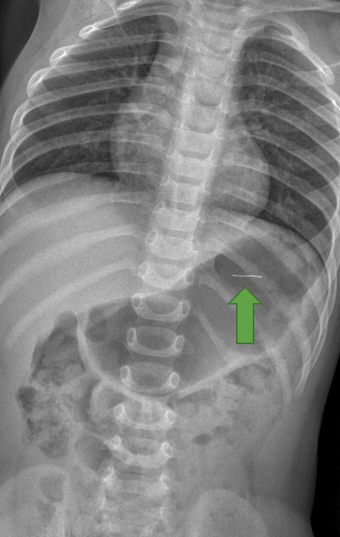

Confermata radiograficamente la presenza del corpo estraneo (Figura 1) e individuata la posizione nello stomaco, veniva effettuato prelievo ematochimico al T0 e, in accordo con i chirurghi pediatrici, disposta osservazione per le successive 24 ore per la possibile comparsa di sintomi quali nausea, vomito e dolore addominale.